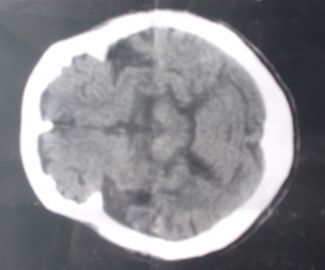

そんな、母の脳の状態。 医師からは、だいぶ収縮しているとの見解。

_

私たちが、見ても判らないが、脳の中に白い物があるのは確認できます。